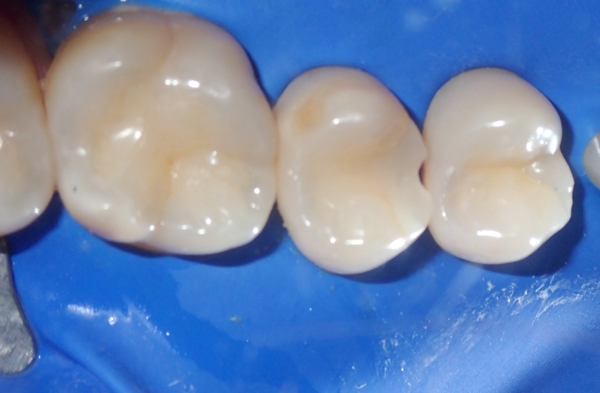

After removing the matrix system, the contacts were carefully verified using floss to ensure proper interproximal alignment. Occlusion was then assessed with articulating paper to confirm accurate bite relationships. Margins were refined using fine-grit diamond burs and carbide finishing burs to enhance precision and smooth transitions. A final polish was achieved through a multi-step polishing system designed to deliver optimal smoothness and luster. This polishing protocol included the use of Rally Polishers (Garrison Dental), A.S.A.P. Polishers (Clinician's Choice), and composite polishing paste for a high-quality, esthetic finish (Fig. 8-11).

The final restorations demonstrated tight, anatomically correct proximal contacts, ensuring proper tooth alignment and function. They also exhibited excellent marginal adaptation and a high-quality polish, contributing to both durability and esthetics. Additionally, the restorations maintained functional occlusion, resulting in high patient satisfaction with both comfort and appearance (Fig. 12).

FIG. 8

FIG. 9

FIG. 10

FIG. 11

FIG. 12

Restorations exhibit tight proximal contacts, smooth surfaces, and natural anatomy, ensuring

function and esthetics.